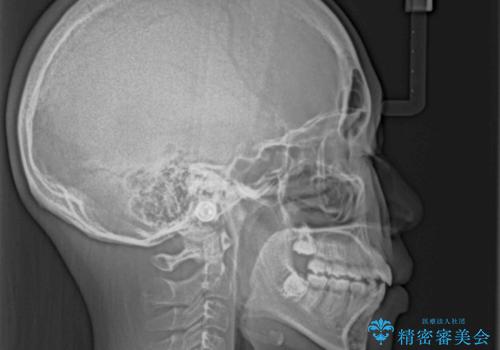

舌突出癖で出っ歯と開咬に 舌のトレーニングを行いながら抜歯矯正

舌の突出癖により上下前歯は接触できず、更には前方に押し出されて出っ歯になっている状態でした。

上下左右の第一小臼歯4本を抜歯し、ワイヤー装置での抜歯矯正を行っていくのですが、原因である舌の突出癖を改善しないことには治療がうまく進められないため、舌のトレーニングを徹底するよう指導していくこととしました。

当初は舌のトレーニングがうまくできていなかったのですが、途中から奏効し、非常に短い期間で治療を終えることができました。